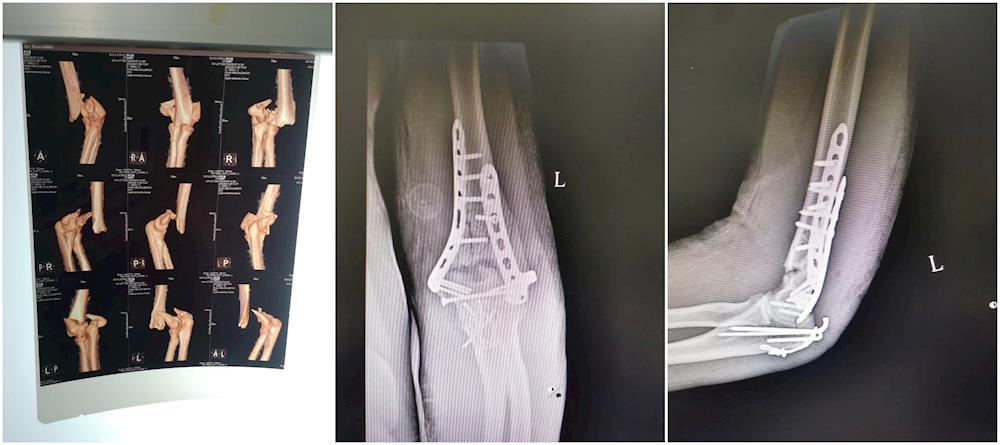

成功救治左侧肱骨远端粉碎性骨折患者

近日,桂林市第二人民医院创伤骨科·手足显微外科成功实施一例左侧肱骨远端粉碎性骨折手术。

当天,家住桂林的李先生在骑行电动车时时不慎摔倒,左侧肘部着地,当时即感觉左肘部疼痛肿胀,被送往桂林市第二人民医院创伤骨科·手足显微外科救治,到院后,医师立即给予相应检查,诊断为“左侧肱骨远端粉碎性骨折”且骨折端位置严重错位。在与患者家属沟通后,为患者进行手术治疗。

对患者实行左侧肱骨远端粉碎性骨折切开复位钢板内固定术

手术时机成熟后,患者被送入手术室,开展左侧肱骨远端粉碎性骨折切开复位钢板内固定术,经过几个小时的努力,手术成功。术后复查X光片,显示骨折复位良好,关节面平整,钢板螺钉内固定位置合适。经过医护人员的精心治疗护理,目前,患者术后恢复良好,已康复出院。